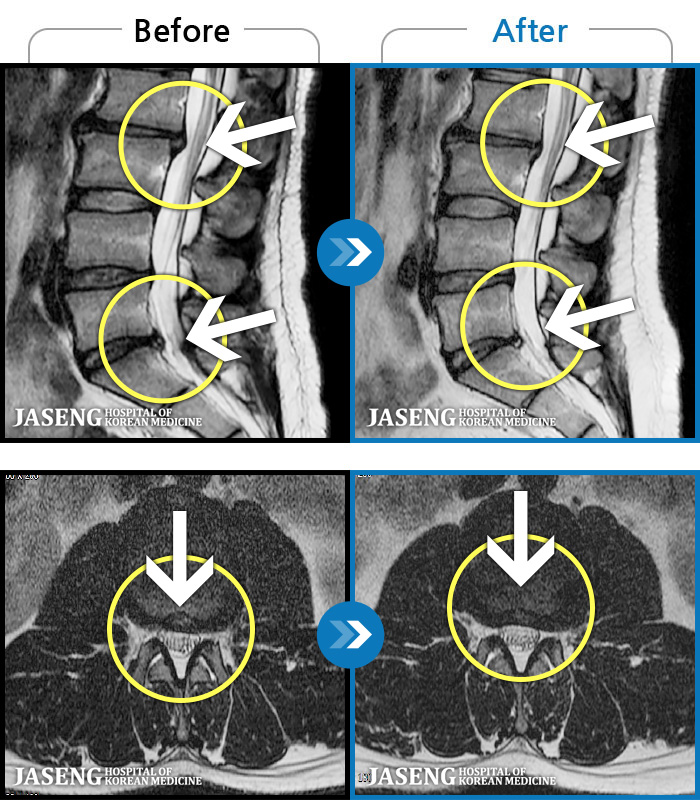

MRI ġ

1,301 MRI ũ ʸ Ȯϼ.